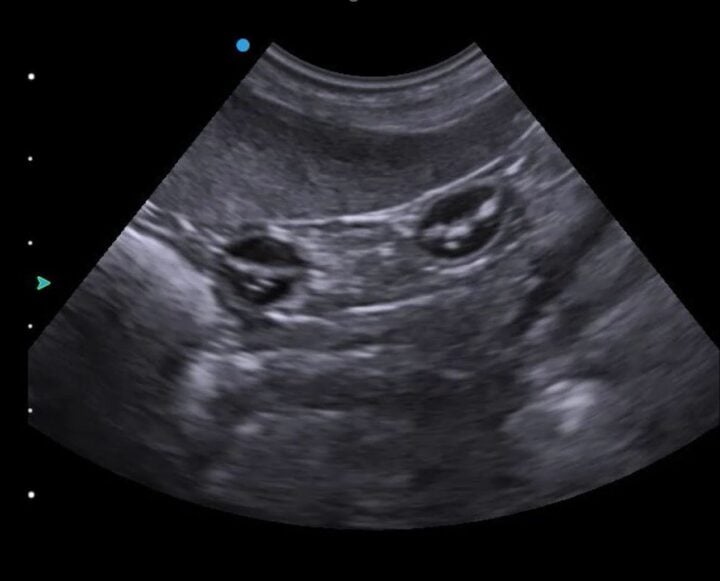

Intestines or gestation sacs? Manipulating the imaging plane

Once you have identified and looked around the bladder and as you begin to move your transducer cranially, you will encounter either more gestation sacs or the intestines (Figure 2) in the “normal” bitch or queen. Intestines are one of the great pitfalls of pregnancy scanning and are mistaken for gestation sacs more often than you might care to believe. The key is to rotate your transducer 90 degrees to confirm whether the circular structure you are seeing is indeed spherical (ie an early gestation sac).

Manipulating your imaging plane is essential for certain measurements, such as crown–rump length and biparietal diameter. Still images can be ambiguous – Figure 3, for example, is not pregnancy – so watching a video clip (Video 1) instead makes this image more interpretable.